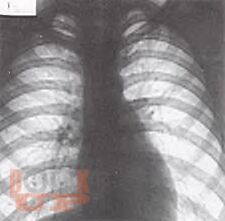

В части II представлен учебный материал по темам «Хронический необструктивный бронхит. Хроническая обструктивная болезнь легких.

Бронхиальная астма». По каждой теме изложены современные научные данные по этиологии, патогенезе, классификации, клинике, методах диагностики, лечения и профилактики заболеваний, способствующие формированию у обучающихся общепрофессиональных компетенций ОПК-4, ОПК-5, ОПК-7 и профессиональных компетенций ПК-5, ПК-6, ПК-8, ПК-10, ПК-11. Для самоконтроля обучающимися сформированности компетенций предложены тестовые задания и ситуационные задачи с эталонами ответов, составленные авторами по учебному материалу с учетом индикаторов достижения компетенций.